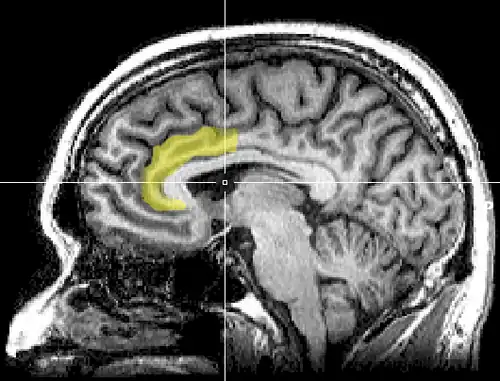

Cognitive dissonance produces a state of negative affect, which motivates the person to reconsider the causative behavior in order to resolve the psychological inconsistency that caused the mental stress.[125][126][127][128][129][130] As the affected person works towards a behavioral commitment, the motivational process then is activated in the left frontal cortex of the brain.[125][126][127][131][129]

The results of the neural scan experiment support the original theory of Cognitive Dissonance proposed by Festinger in 1957; and also support the psychological conflict theory, whereby the anterior cingulate functions, in counter-attitudinal response, to activate the dorsal anterior cingulate cortex and the anterior insular cortex; the degree of activation of said regions of the brain is predicted by the degree of change in the psychological attitude of the person.[133]

The biomechanics of cognitive dissonance: MRI evidence indicates that the greater the psychological conflict signalled by the anterior cingulate cortex, the greater the magnitude of the cognitive dissonance experienced by the person.

As an application of the free-choice paradigm, the study How Choice Reveals and Shapes Expected Hedonic Outcome (2009) indicates that after making a choice, neural activity in the striatum changes to reflect the person's new evaluation of the choice-object; neural activity increased if the object was chosen, neural activity decreased if the object was rejected.[134] Moreover, studies such as The Neural Basis of Rationalization: Cognitive Dissonance Reduction During Decision-making (2010)[48] and How Choice Modifies Preference: Neural Correlates of Choice Justification (2011) confirm the neural bases of the psychology of cognitive dissonance.[121][135]

The Neural Basis of Rationalization: Cognitive Dissonance Reduction During Decision-making[48] (Jarcho, Berkman, Lieberman, 2010) applied the free-choice paradigm to fMRI examination of the brain's decision-making process whilst the study participant actively tried to reduce cognitive dissonance. The results indicated that the active reduction of psychological dissonance increased neural activity in the right-inferior frontal gyrus, in the medial fronto-parietal region, and in the ventral striatum, and that neural activity decreased in the anterior insula.[48] That the neural activities of rationalization occur in seconds, without conscious deliberation on the part of the person; and that the brain engages in emotional responses whilst effecting decisions.[48]

Emotional correlations

The results reported in Contributions from Research on Anger and Cognitive Dissonance to Understanding the Motivational Functions of Asymmetrical Frontal Brain Activity[136] (Harmon-Jones, 2004) indicate that the occurrence of cognitive dissonance is associated with neural activity in the left frontal cortex, a brain structure also associated with the emotion of anger; moreover, functionally, anger motivates neural activity in the left frontal cortex.[126][34] Applying a directional model of Approach motivation, the study Anger and the Behavioural Approach System (2003) indicated that the relationship between cognitive dissonance and anger is supported by neural activity in the left frontal cortex that occurs when a person takes control of the social situation causing the cognitive dissonance. Conversely, if the person cannot control or cannot change the psychologically stressful stimulation, they are without a motivation to change the circumstance, then there arise other, negative emotions to manage the cognitive dissonance, such as socially inappropriate behavior.[126][137][136]

The anterior cingulate cortex activity increases when errors occur and are being monitored as well as having behavioral conflicts with the self-concept as a form of higher-level thinking.[138] A study was done to test the prediction that the left frontal cortex would have increased activity. University students had to write a paper depending on if they were assigned to a high-choice or low-choice condition. The low-choice condition required students to write about supporting a 10% increase in tuition at their university. The point of this condition was to see how significant the counter-choice may affect a person's ability to cope. The high-choice condition asked students to write in favor of tuition increase as if it were their completely voluntary choice. The researchers use EEG to analyze students before they wrote the essay, as dissonance is at its highest during this time (Beauvois and Joule, 1996). High-choice condition participants showed a higher level of the left frontal cortex than the low-choice participants. Results show that the initial experience of dissonance can be apparent in the anterior cingulate cortex, then the left frontal cortex is activated, which also activates the approach motivational system to reduce anger.[138][139]